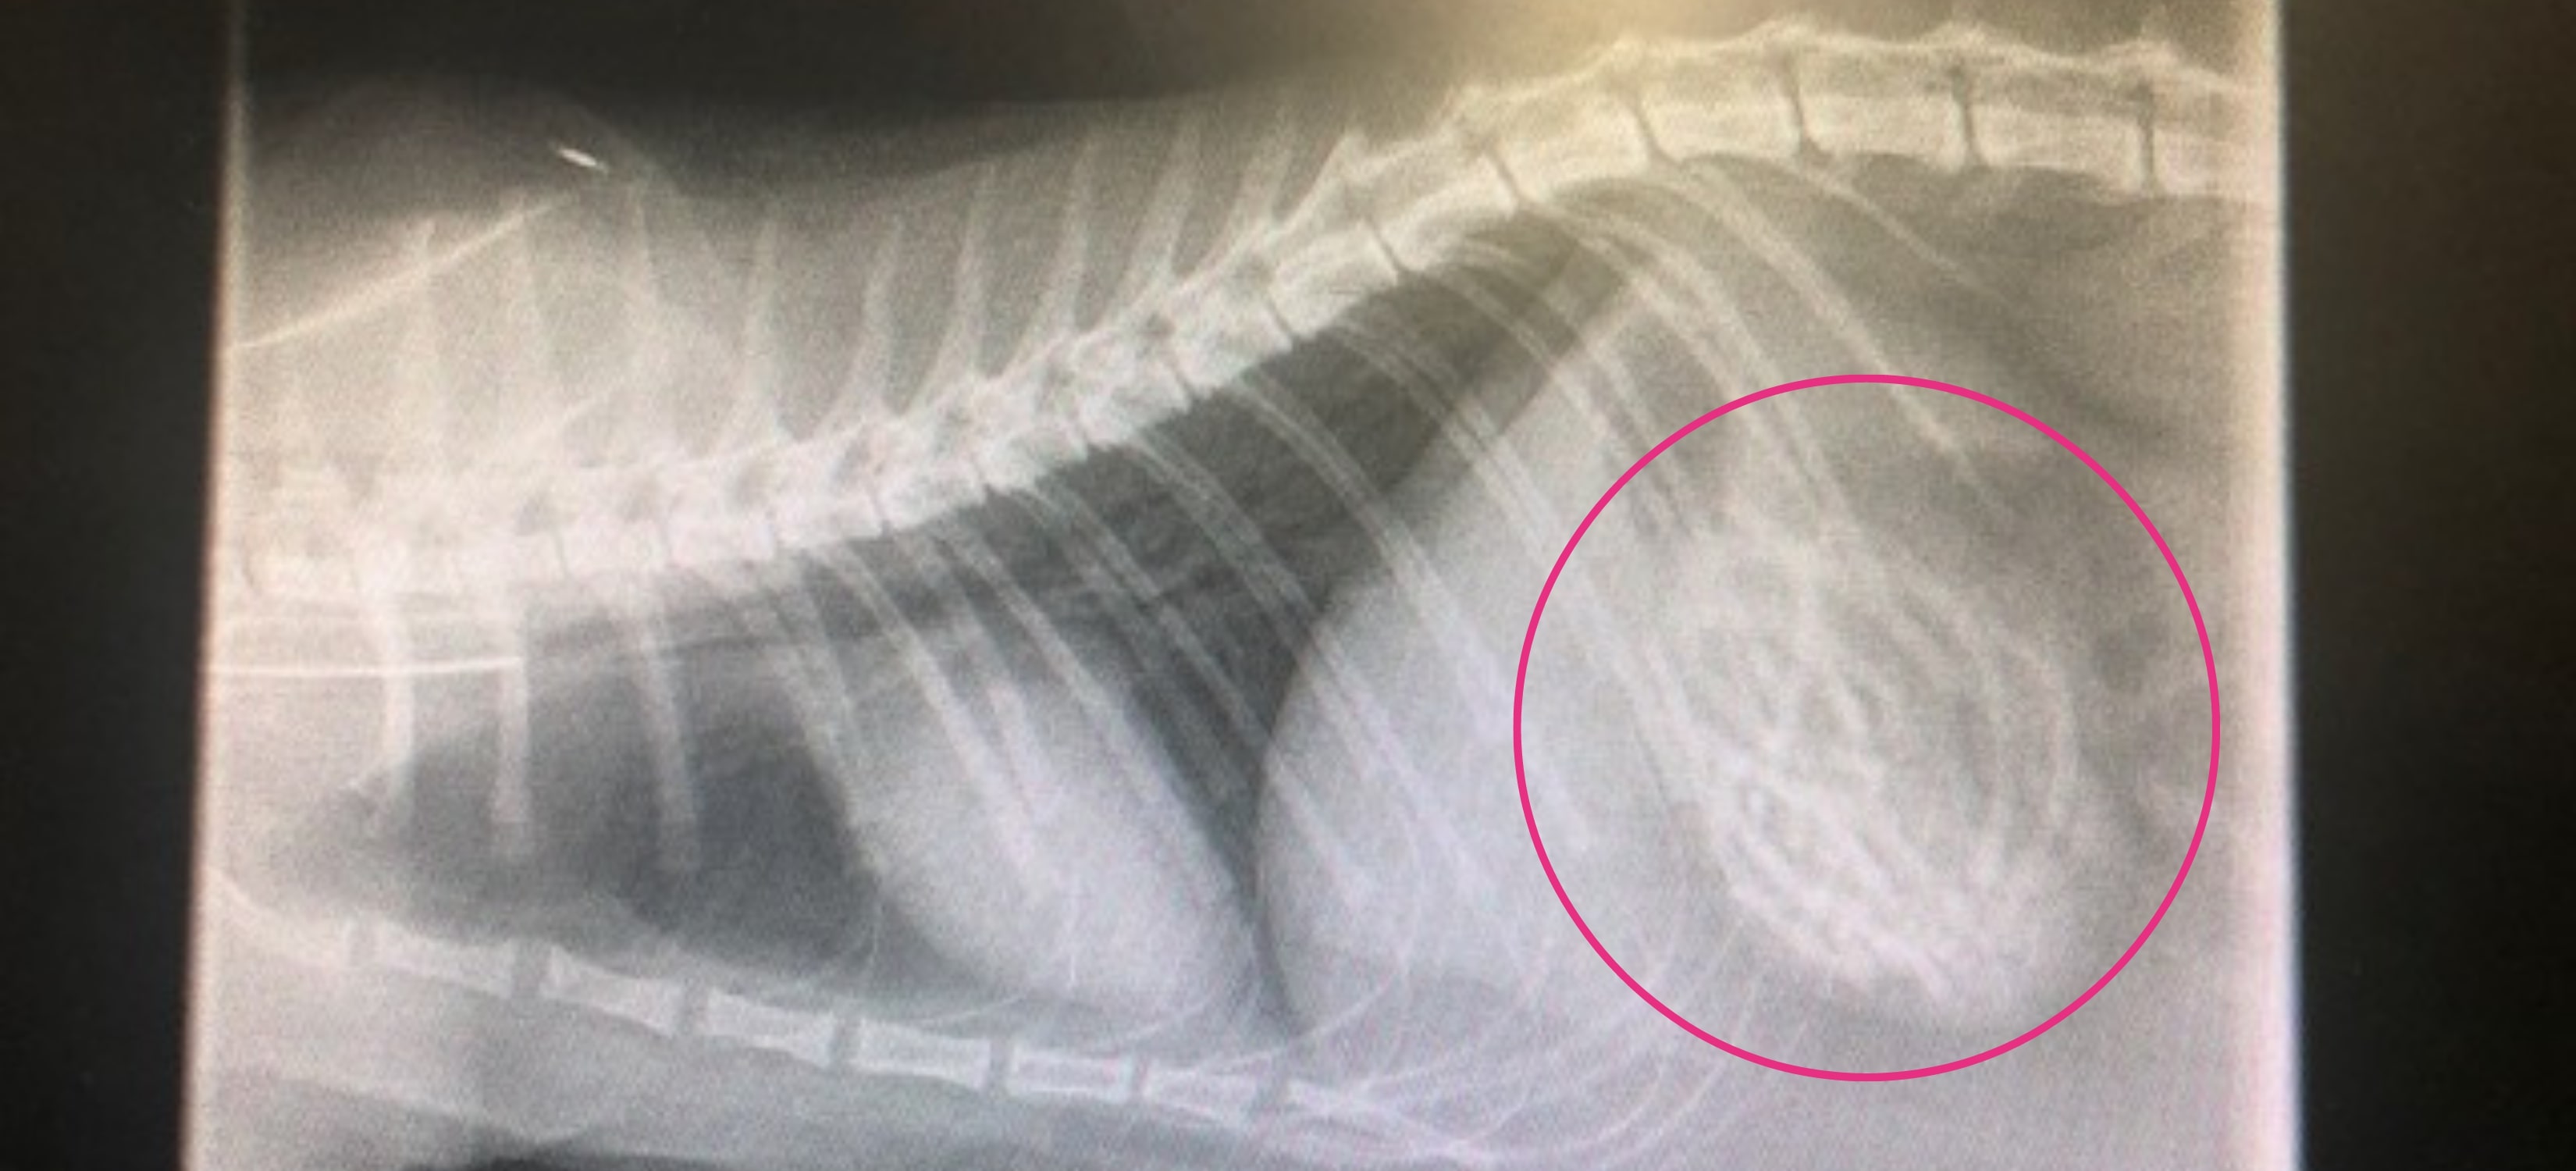

PDSA Vet, Rebecca Lewis, said: "X-rays revealed that there were lots of hairbands in Irwin's stomach, and we were concerned they were obstructing his guts. He needed emergency surgery to remove them right away. One of the problems with soft foreign bodies, such as hairbands or cloth, is that they are challenging to detect when examining a pet; fortunately for Irwin, we could see the cause of the blockage on his x-rays. After an intense operation, we successfully removed the hairbands, and Irwin was kept at the hospital for a few days for monitoring."